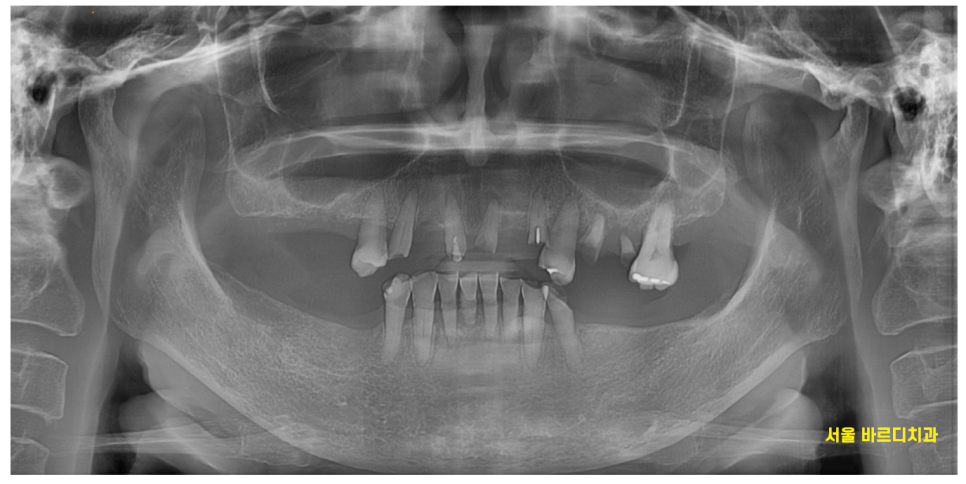

23.08.17

23.08.17 환자분을 처음 보았습니다.

어금니 치아는 위 아래 다 빠져있는 상황

남아 있는 치아 중에서도

문제가 많았습니다.

노랗게 삭아버렸거나

뿌리만 남아있는 치아도 많았는데요.

아래 치아의 경우 깨지고

치아가 뽑힌지 오래되어 잇몸뼈가 얼마 없는 상황이었습니다.

거리가 멀어 자주 오실 수 없는 상황이라

전악 임플란트를 진행하기로 결정하였습니다.